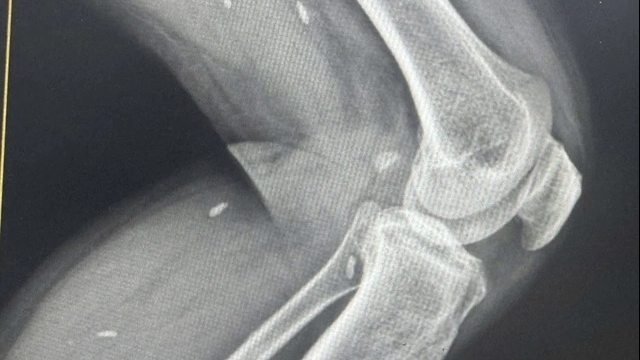

Ngay khi nhập viện hội chẩn nhiều chuyên khoa với chẩn đoán viêm ruột thừa cấp nhồi máu cơ tim cấp (nhồi máu cơ tim không ST chênh lên đã dùng thuốc chống đông). Cả hai bệnh đều là bệnh lý cấp cứu, tuy nhiên do nhồi máu cơ tim hiện ổn định nguy cơ thấp nên việc can thiệp sẽ thực hiện trong vòng 24 giờ, ê kíp quyết định phẫu thuật cấp cứu ruột thừa trước.

Bệnh nhân có yếu tố nguy cơ rất cao về tim mạch và nguy cơ chảy máu. Phẫu thuật nội soi thấy khối áp xe kích thước 5x5 cm ở hố chậu phải, tách ổ áp xe nhiều mủ trắng đục, ruột thừa sau manh tràng hoại tử vỡ ở thân tạo ổ áp xe. Do vị trí ruột thừa sau manh tràng nên thời gian phẫu thuật kéo dài trong 2 giờ. Bác sĩ tiến hành cắt ruột thừa gửi Khoa Giải phẫu bệnh.

Bệnh nhân được thực hiện các cận lâm sàng cần thiết, tiến hành hội chẩn phẫu thuật với chẩn đoán: Viêm ruột thừa cấp, nhồi máu cơ tim cấp (nhồi máu cơ tim không ST chênh lên nguy cơ thấp- huyết động ổn định). Các bác sĩ đã phẫu thuật nội soi cấp cứu thành công cắt ruột thừa bị viêm, mưng mủ.